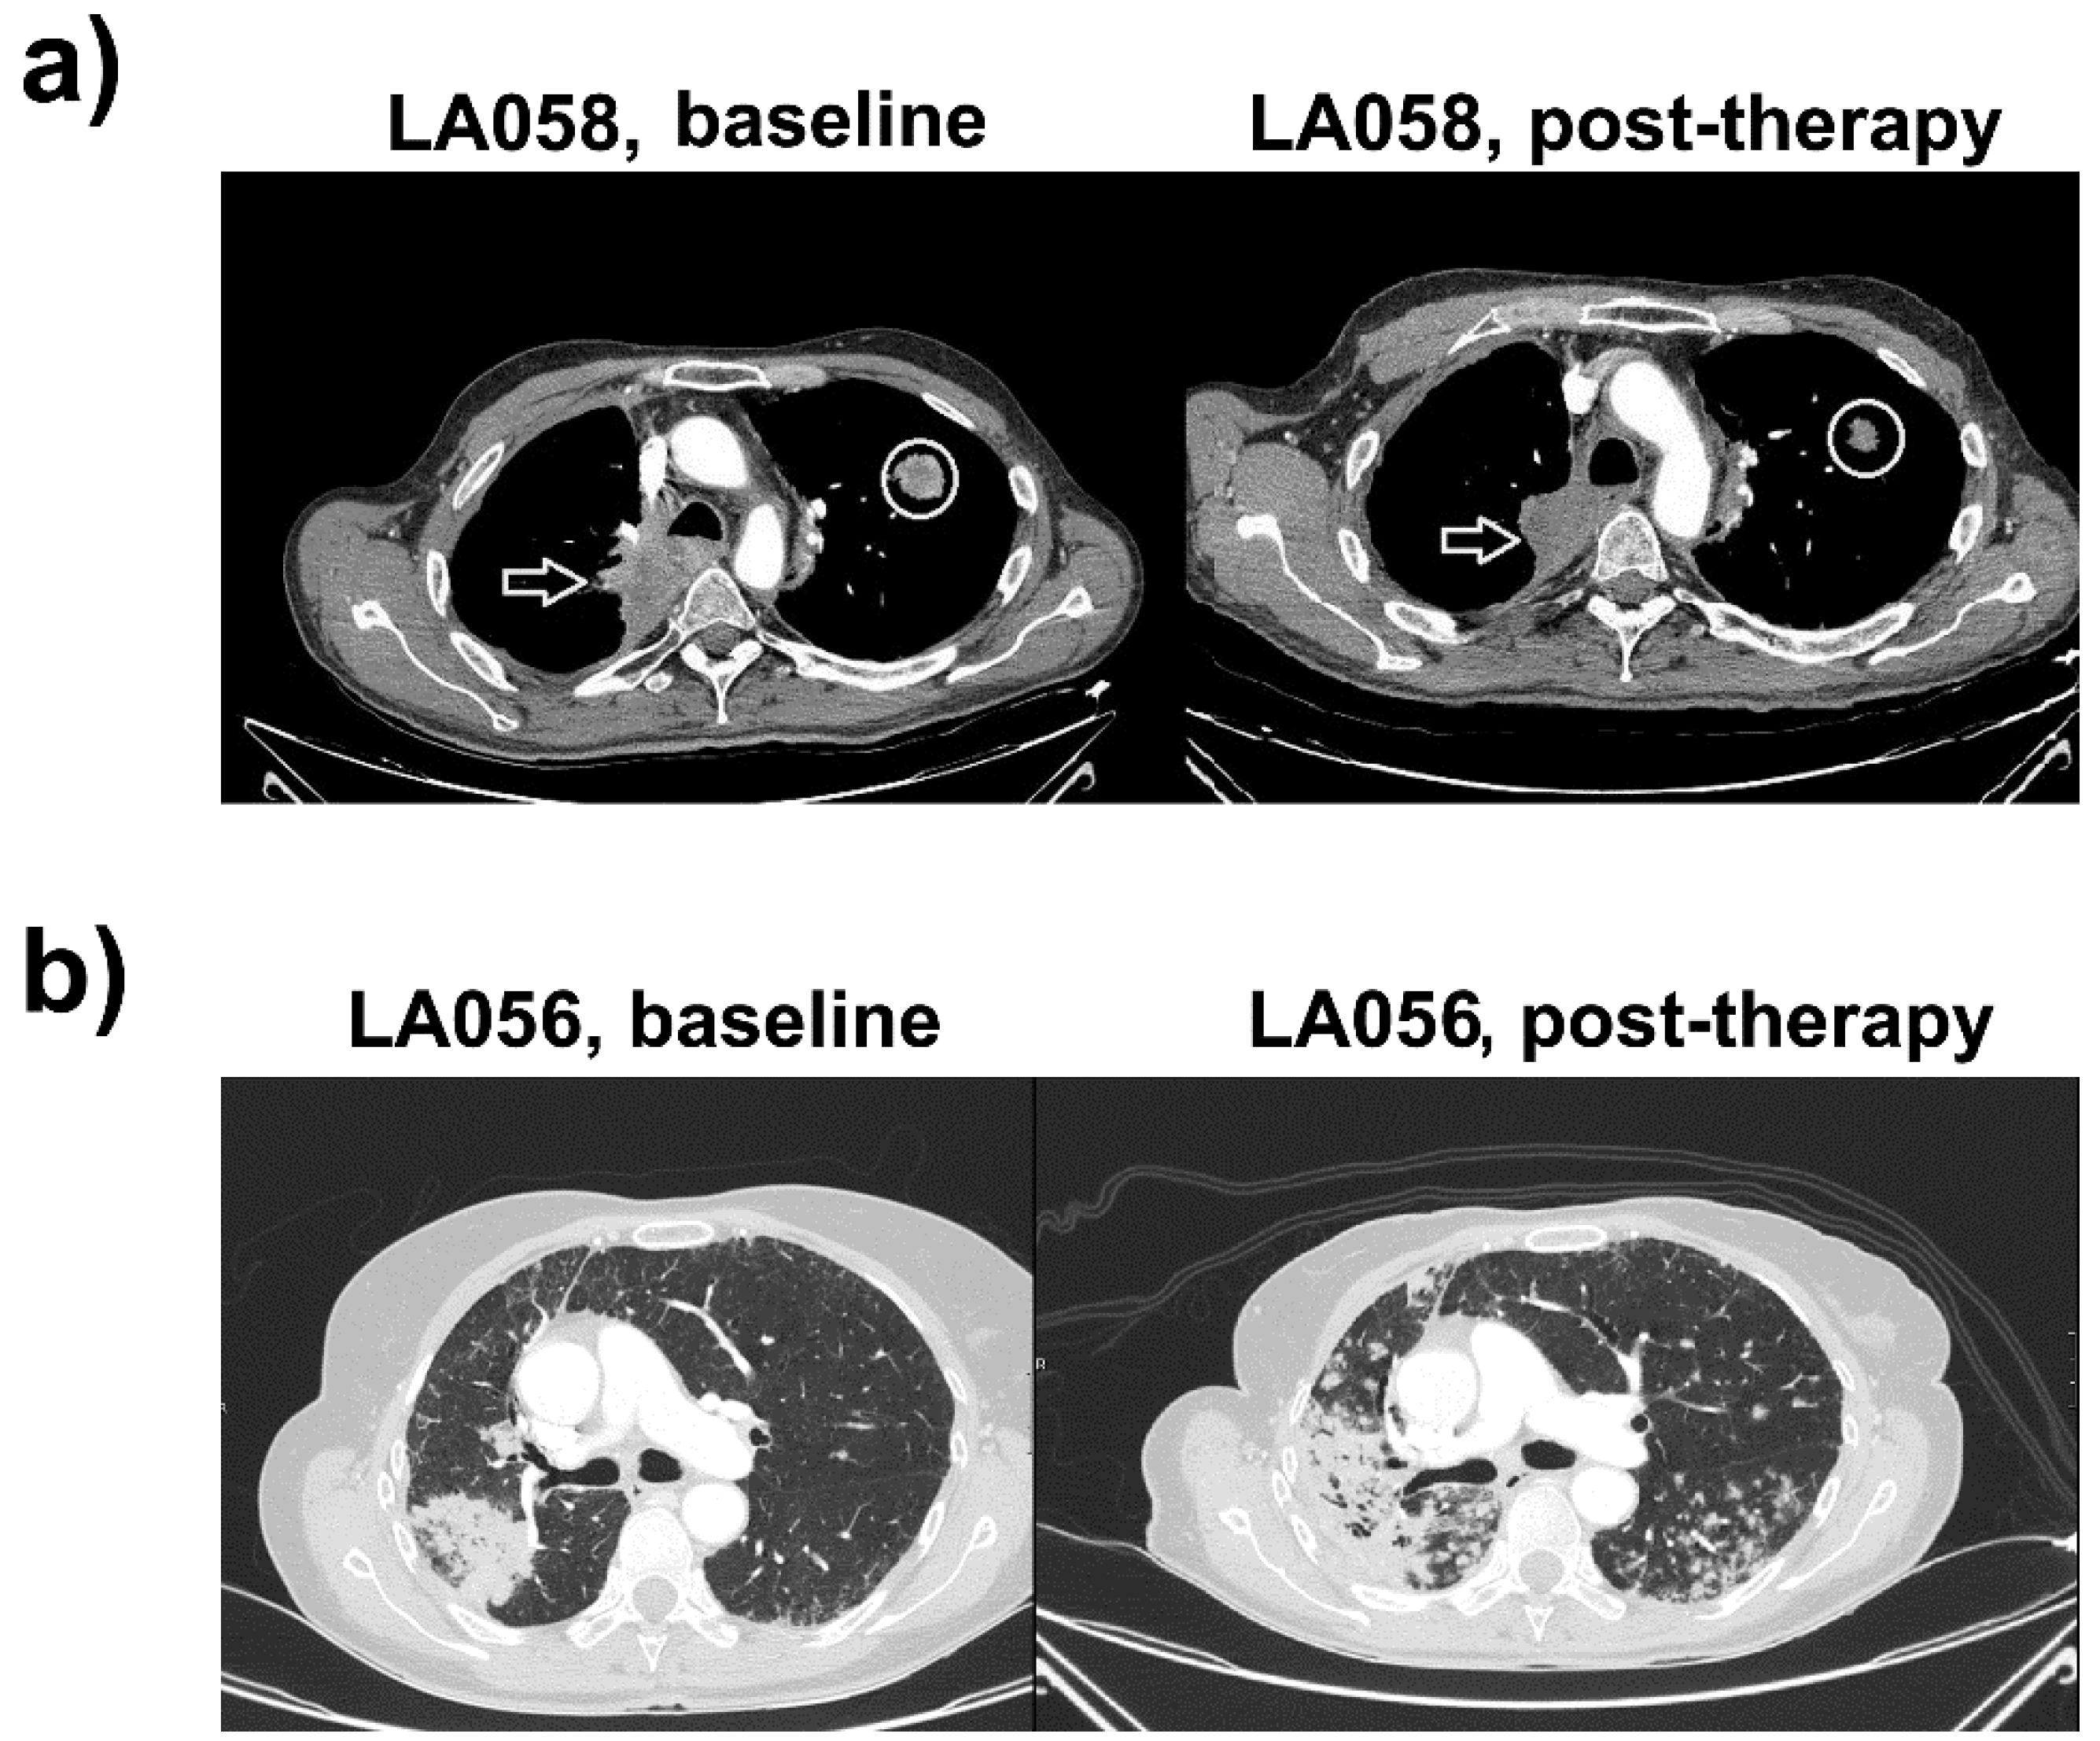

2.1. Case Study 1. Objective Responder

2.2. Case Study 2. Progressor